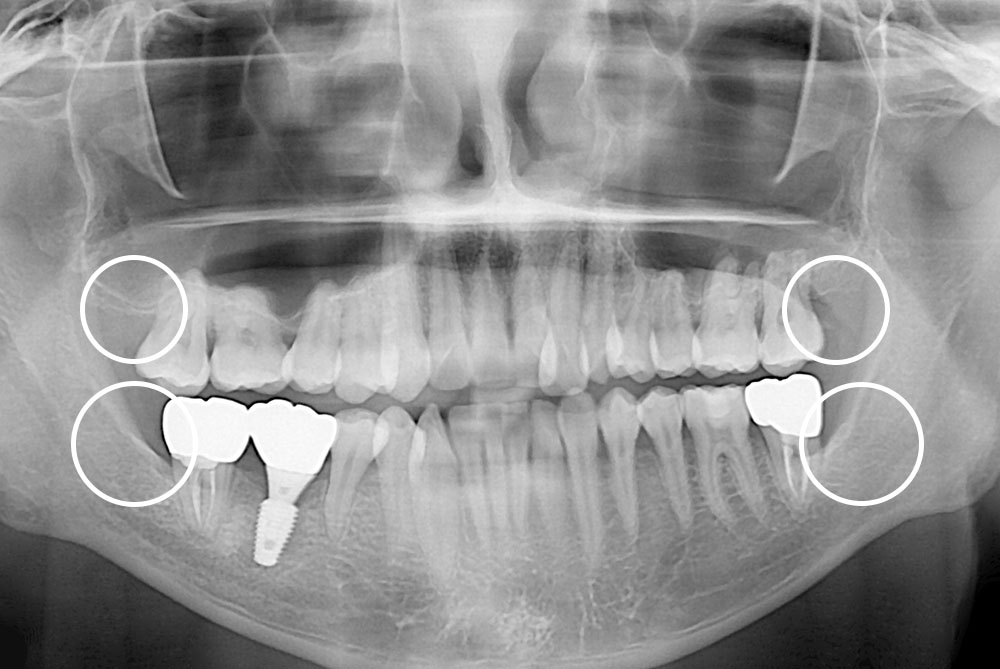

[사랑니] 매복 사랑니 발치

치료전 : 2019-05-01